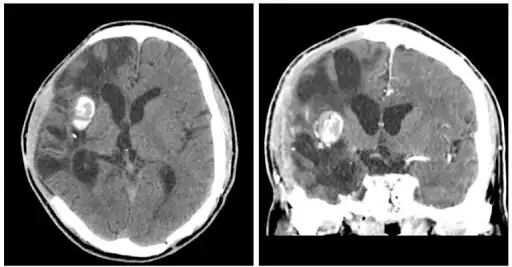

Brain abscess after metastasis treatment.

The diagnosis is established by a computed tomography (CT) (with contrast) examination. At the initial phase of the inflammation (which is referred to as cerebritis), the immature lesion does not have a capsule and it may be difficult to distinguish it from other space-occupying lesions or infarcts of the brain. Within 4–5 days the inflammation and the concomitant dead brain tissue are surrounded with a capsule, which gives the lesion the famous ring-enhancing lesion appearance on CT examination with contrast (since intravenously applied contrast material can not pass through the capsule, it is collected around the lesion and looks as a ring surrounding the relatively dark lesion). Lumbar puncture procedure, which is performed in many infectious disorders of the central nervous system is contraindicated in this condition (as it is in all space-occupying lesions of the brain) because removing a certain portion of the cerebrospinal fluid may alter the concrete intracranial pressure balances and causes the brain tissue to move across structures within the skull (brain herniation).

Ring enhancement may also be observed in cerebral hemorrhages (bleeding) and some brain tumors. However, in the presence of the rapidly progressive course with fever, focal neurologic findings (hemiparesis, aphasia etc.) and signs of increased intracranial pressure, the most likely diagnosis should be the brain abscess.